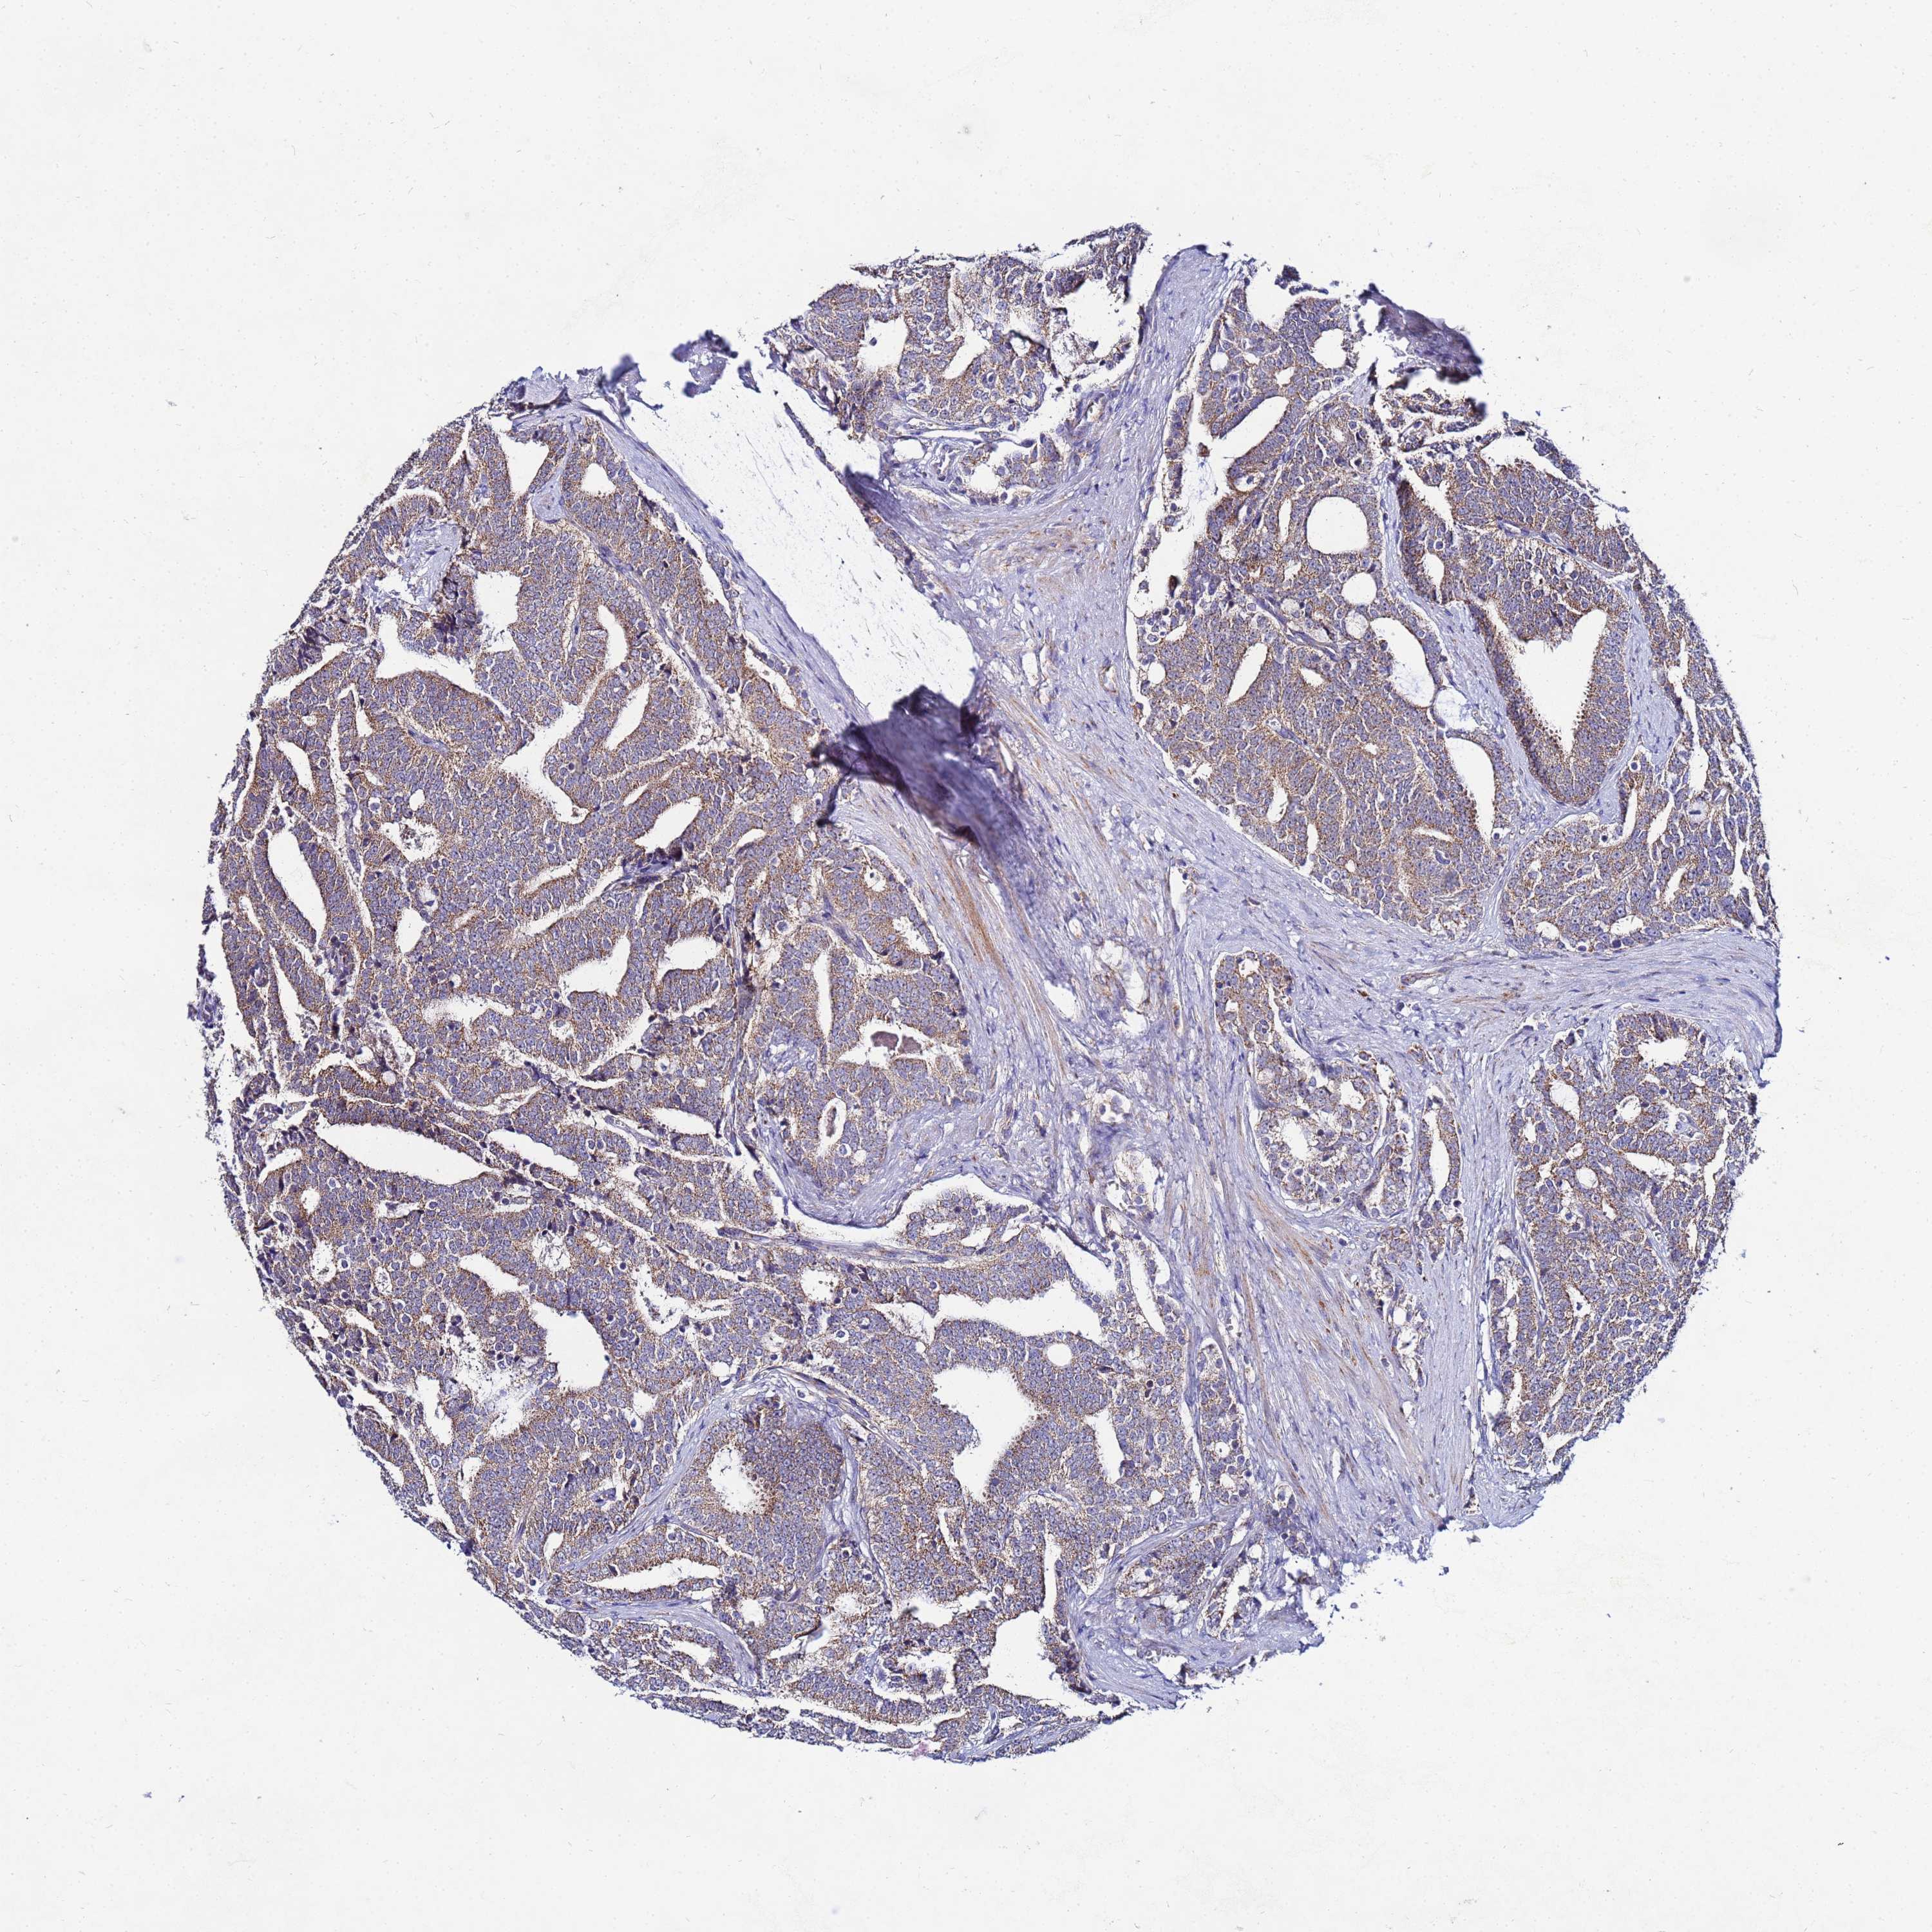

PROSTATE CANCER - Protein expressioni

A mouse-over function shows sample information and annotation data. Click on an image to view it in a full screen mode. Samples can be filtered based on level of antibody staining by selecting one or several of the following categories: high, medium, low and not detected. The assay and annotation is described here.

Antibody stainingi

Antibody staining in the annotated cell types in the current human tissue is reported as not detected, low, medium, or high, based on conventional immunohistochemistry profiling in selected tissues. This score is based on the combination of the staining intensity and fraction of stained cells.

Each image is clickable and will lead to virtual microscopy that enables deeper exploration of all samples and also displays staining intensity scores, fraction scores and subcellular localization as well as patient and tissue information for each sample.

Antibody HPA042145

Antibody HPA044987

Antibody CAB045971

Antibody CAB045972

Staining

High

Medium

Low

Not detected

Intensity

Strong

Moderate

Weak

Negative

Quantity

>75%

75%-25%

<25%

None

Location

Nuclear

Cytoplasmic/membranous

Cytoplasmic/membranous,nuclear

Adenocarcinoma, NOS

Adenocarcinoma, High grade

Adenocarcinoma, Low grade